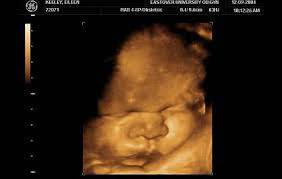

Бебето

39 седмица след първия ден на последния менструален цикъл 38 седмици + 1 – 7 дни (лекарско пресмятане) 37 седмица след оплождането Диаметър на главичката на плода: около90-103 mm Тегло на плода: около 3350 g Дължина на плода: около 49 cm